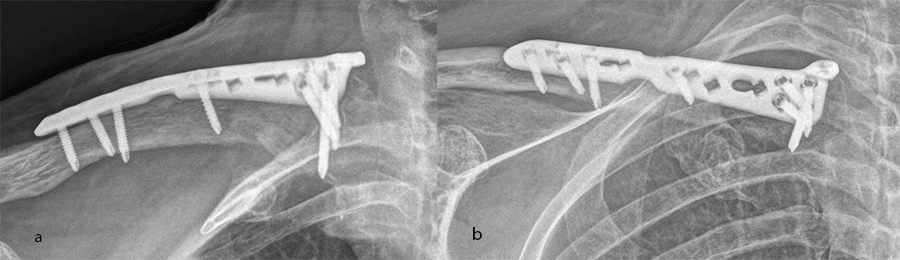

A 60-year-old woman sustained a medial fracture to the left clavicle following a car crash. A computed tomographic (CT) scan was performed 8 weeks after the incident (Fig 17). Intraoperative images reveal plate placement and screw insertion (Fig 18). Image shows the fracture healing at 4 weeks’ follow-up (Fig 19).